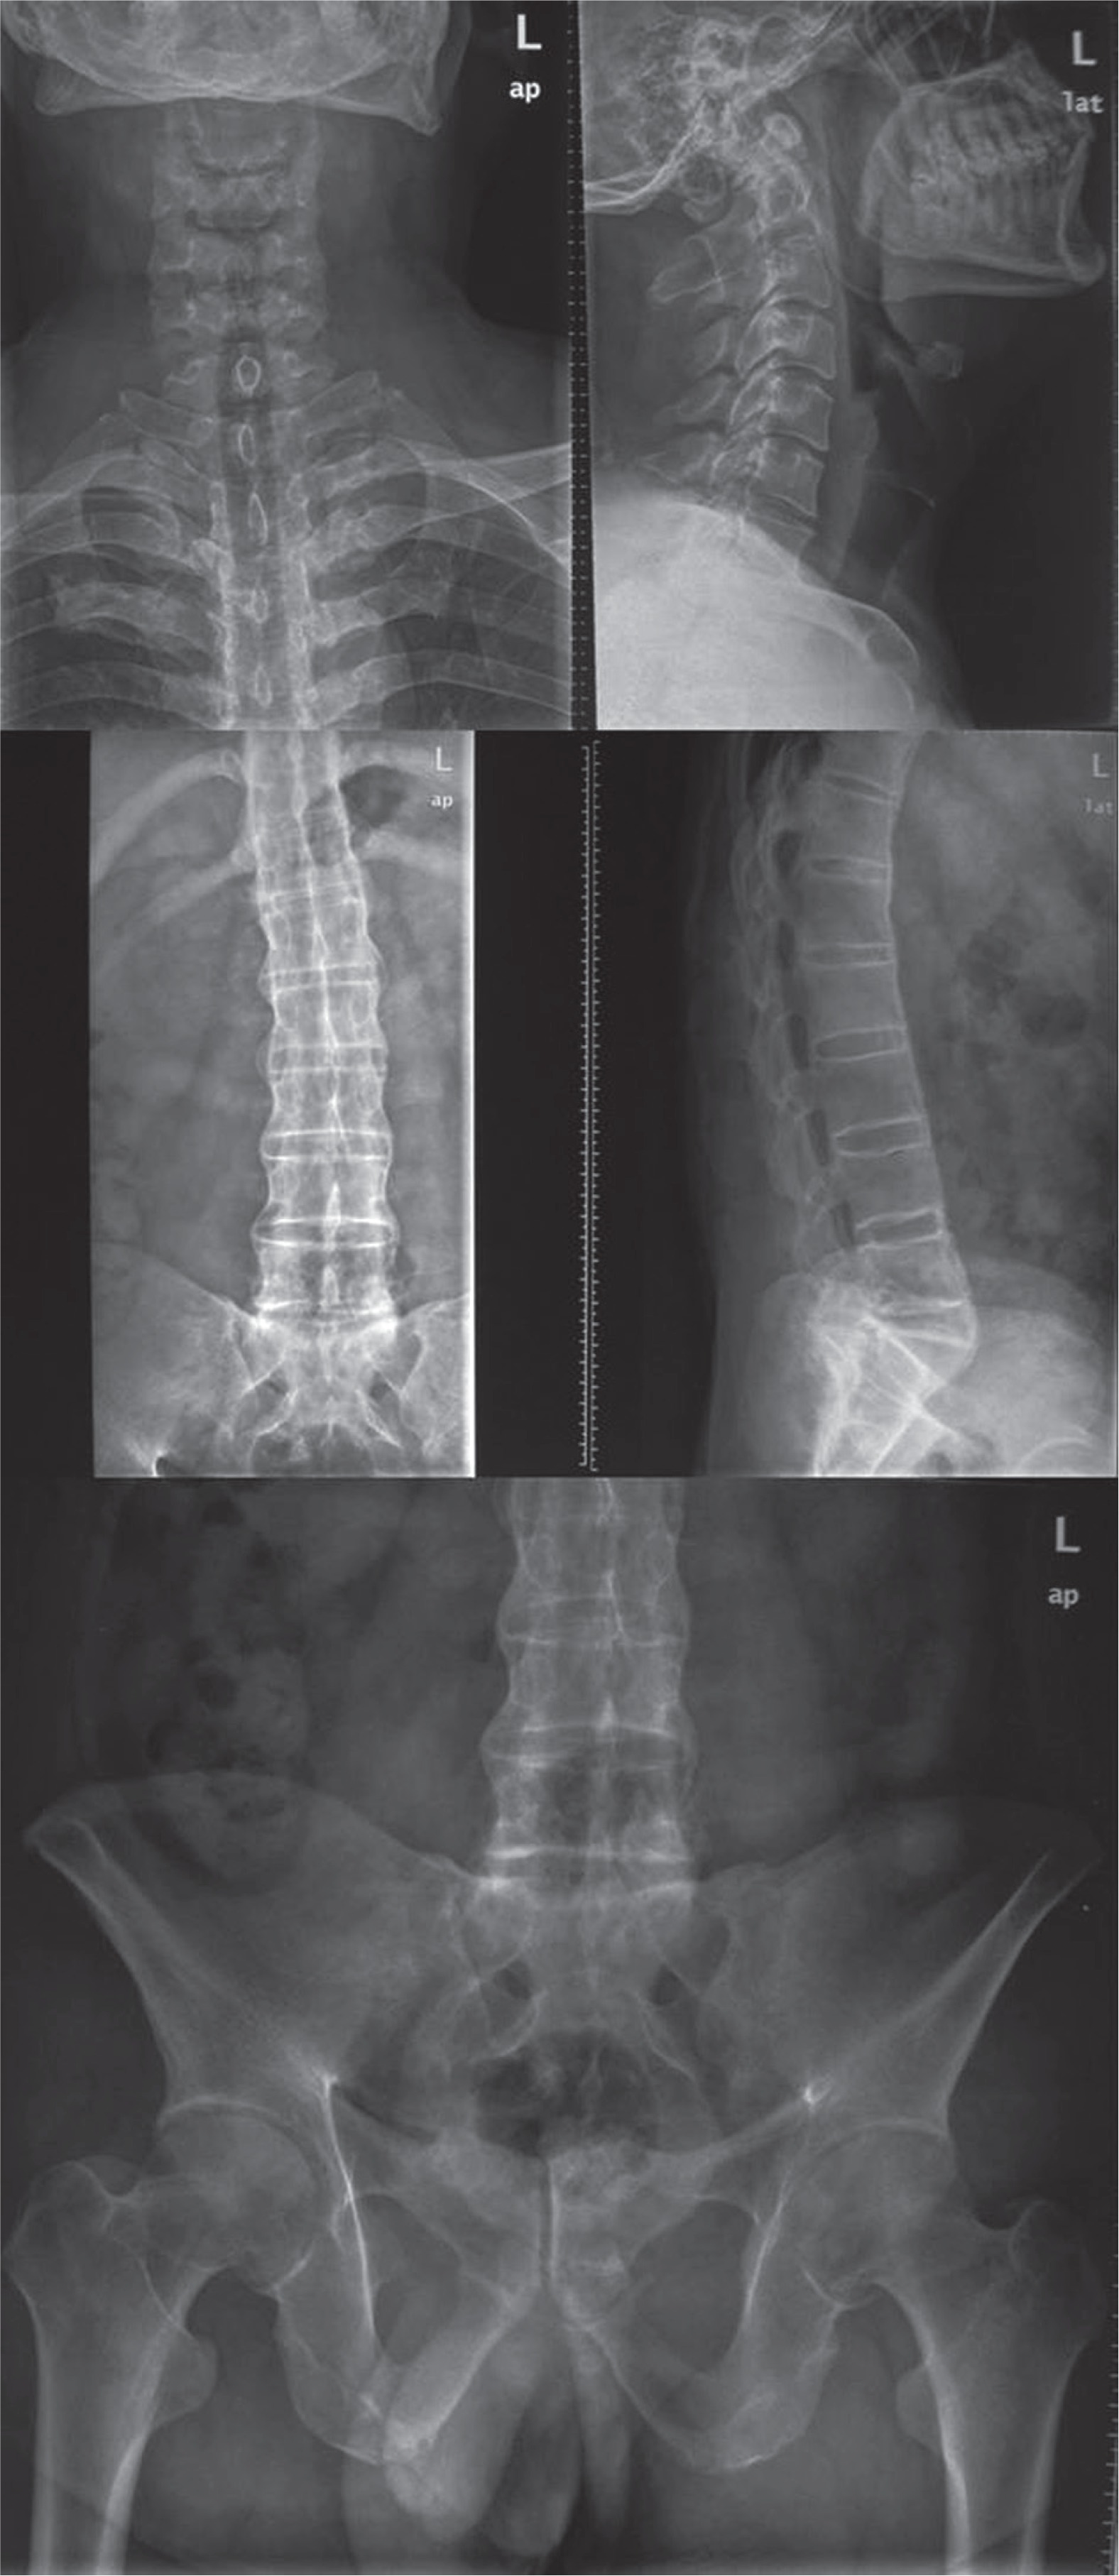

Twenty AS patients and 20 age- and sex-matched healthy controls were included in our study. Characteristics of the study subjects are presented in Table 1. X-ray images showed ankylosis of cervical, lumbar, and spine in the patients (Fig. 1).

Fig. 1

A patient with advanced ankylosis shown in cervical, lumbar, and pelvis X-ray images. Cervical, lumbar, and pelvis X-ray images taken in a patient for diagnosis and mSASSS (modified Stoke Ankylosing Spondylitis Spinal Score) scoring